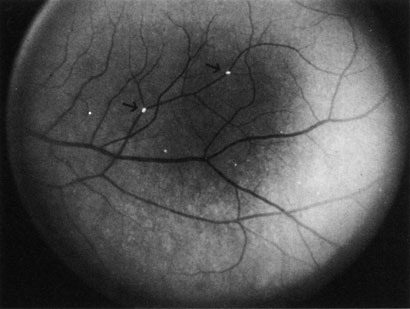

Cilioretinal arteries can be selectively obstructed (Fig. 3). More commonly, however, they occur in association with central retinal vein obstruction.113 When they supply a significant portion of the macula, decreased visual acuity is common. Prognosis for visual outcome in such patients is good. Brown and co-workers114 studied 10 eyes having an isolated cilioretinal artery obstruction. Of those, 60% had an initial visual acuity of 20/40 or better and on follow-up examination, all eyes but one had a best-corrected visual acuity of 20/40 or better.114

Fig. 3. A: Cilioretinal artery obstruction showing opacity of the retina in the area of obstruction. B: The cilioretinal artery has begun to fill after the branches of the central retinal artery but is still not completely filled at this point in the angiogram.